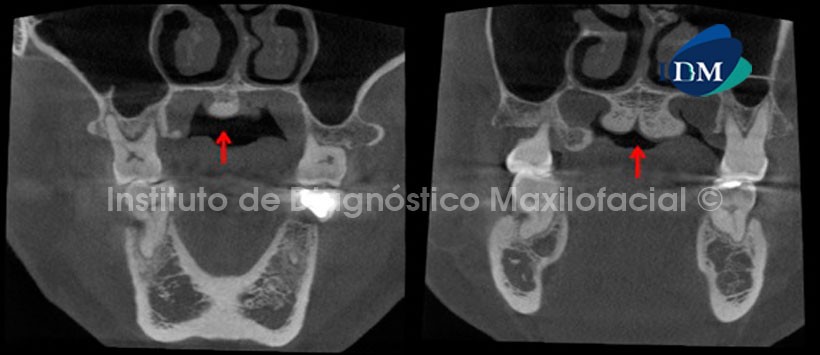

La tomografía computarizada de haz cónico en vistas coronales nos muestra una imagen hiperdensa de forma irregular cuya base se origina en el paladar y que posee características óseas. Signos tomográficos compatibles con Torus Palatino. Se evidencia también zonas de exostosis a nivel de las tablas óseas vestibular y palatina (Fig. 1).